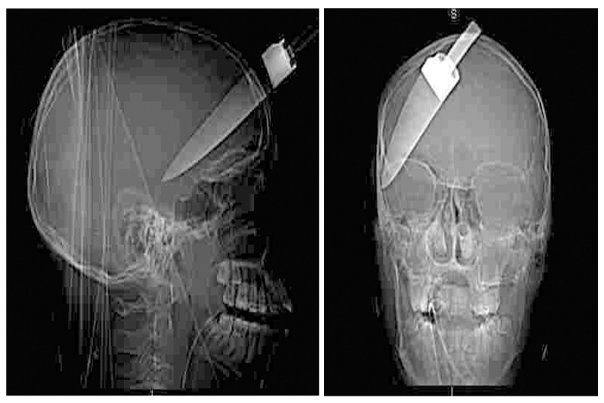

3. Londonska policija objavila je ovu snimku 16-godišnjaka s nožem zabijenim u glavu kako bi upozorila na sve veći problem uličnog nasilja i bandi.